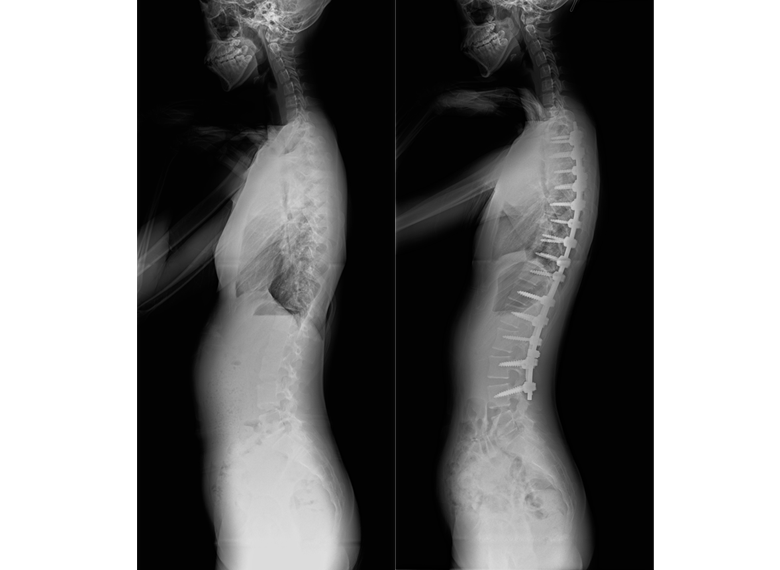

側弯症の手術方法

側弯症の手術方法は、後方矯正固定術(背中から手術する)、前方矯正固定術(お腹側から手術をする)に大別されますが、現在は後方矯正固定術という術式が主流となっています。

後方矯正固定術は、背中の正中部分(真ん中)を切開し、最も傾いている椎体から逆向きに最も傾いている椎体の間にかけて、背骨が見えるように背骨の周囲についている筋肉をはがします。

その後、それぞれの背骨の左右にスクリューを2本ずつ挿入し、それらをロッドと呼ばれるチタン合金やコバルトクロム合金のバーで連結することで側弯を矯正します。各椎体の間にある関節(椎間関節)に、局所の骨や人工骨を移植した後、出血をはじめとする合併症がないことを確認して、傷を閉じます。

術後は、痛みに合わせて2〜3日目から歩いてもらい、傷が塞がって大丈夫と判断された後に退院となります。一般的な入院期間は、10日〜2週間程度です。

側弯症手術にとってもっとも大事なことは、矯正された脊椎がその形で骨癒合することです。自分の骨を移植するのはこのためですが、骨癒合には術後数ヵ月の時間が必要です。よって術後には数ヵ月運動ができなくなります。その後は外来で経過観察しながら、徐々に運動を開始して頂きます。